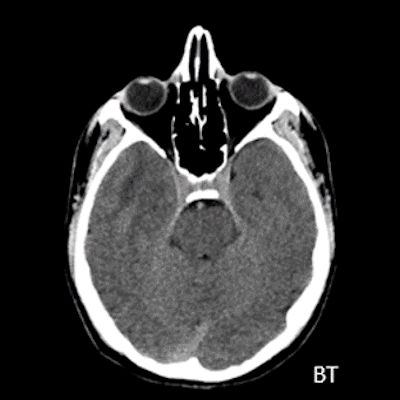

- A) Sağ temporal lob anteromedialinde silik sınırlı BT’de hipodens (ok), MRG’de T2AG ve FLAIR hiperintens (oklar), T1AG izo-hipointens (ok) sinyal özelliğinde ekspansil kitlesel lezyon izlenmektedir.

- BT: Spesifik olmayan kitle bulgularıdır. İzo-hipodens olarak izlenir. Kitle %35 oranında kalsifikasyon gösterebilir. Olgumuzda kalsifikasyon izlenmemiştir. Kemik remodelasyonu da eşlik edebilir.